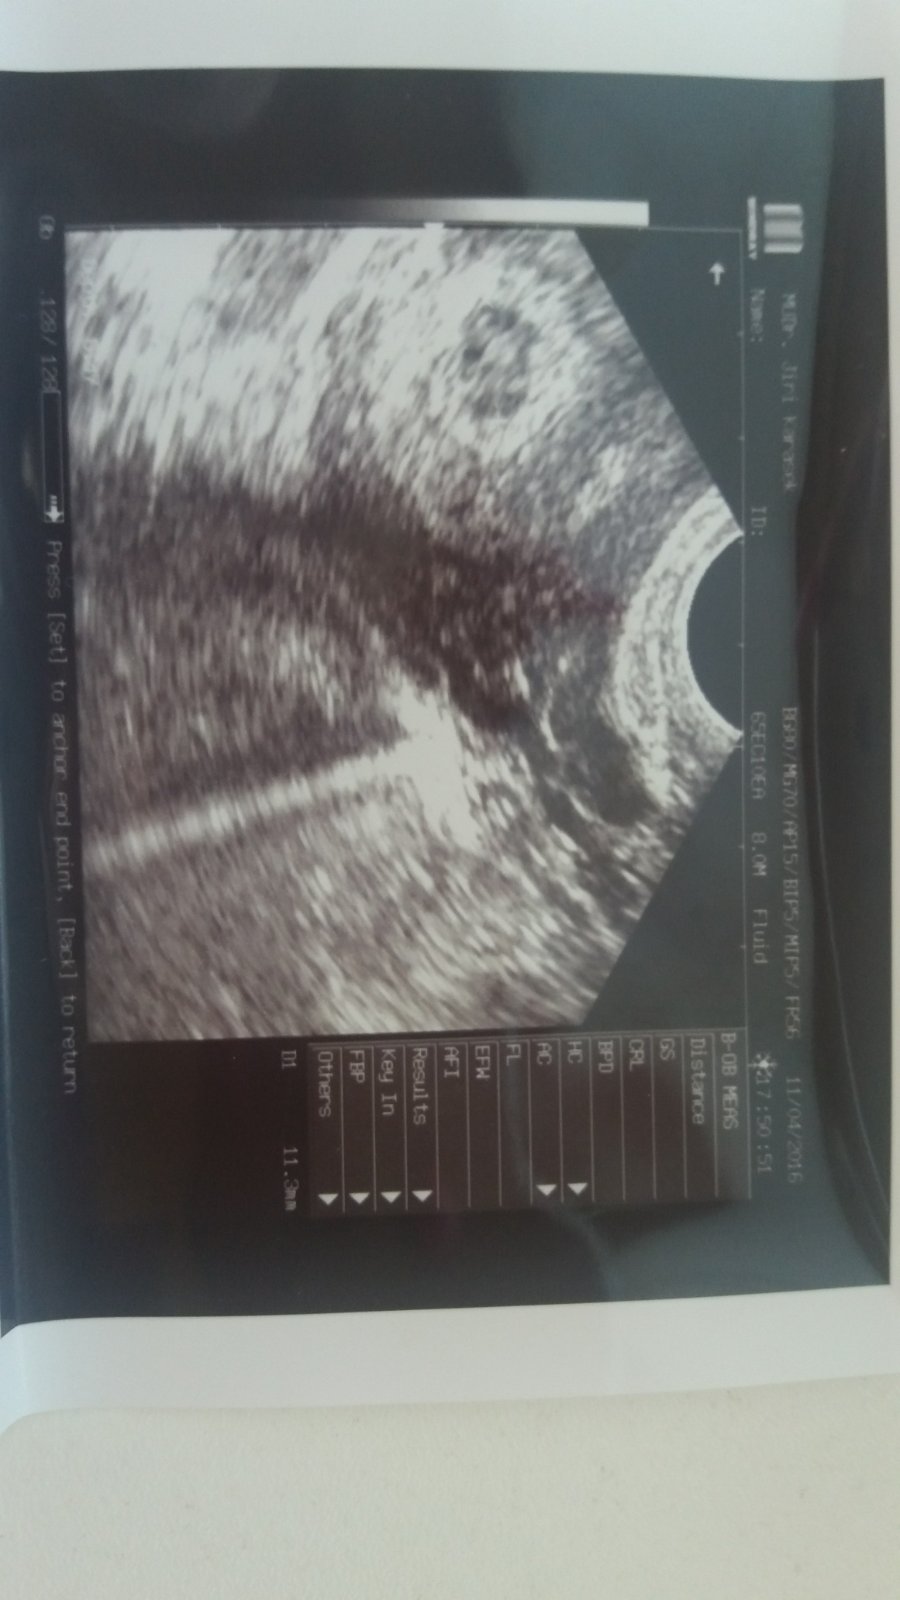

V 6tt je celý váček na ultrazvuku vyplněný šedou barvou

Ahoj holky mám dotaz jsem v 6tt lékař mi našel na kontrole srdíčko ale řekl mi ze celý váček je šedý a je dost pravdepodobny ze dochází ke špatnému vývoji nemáte s tímto někdo zkušenost?